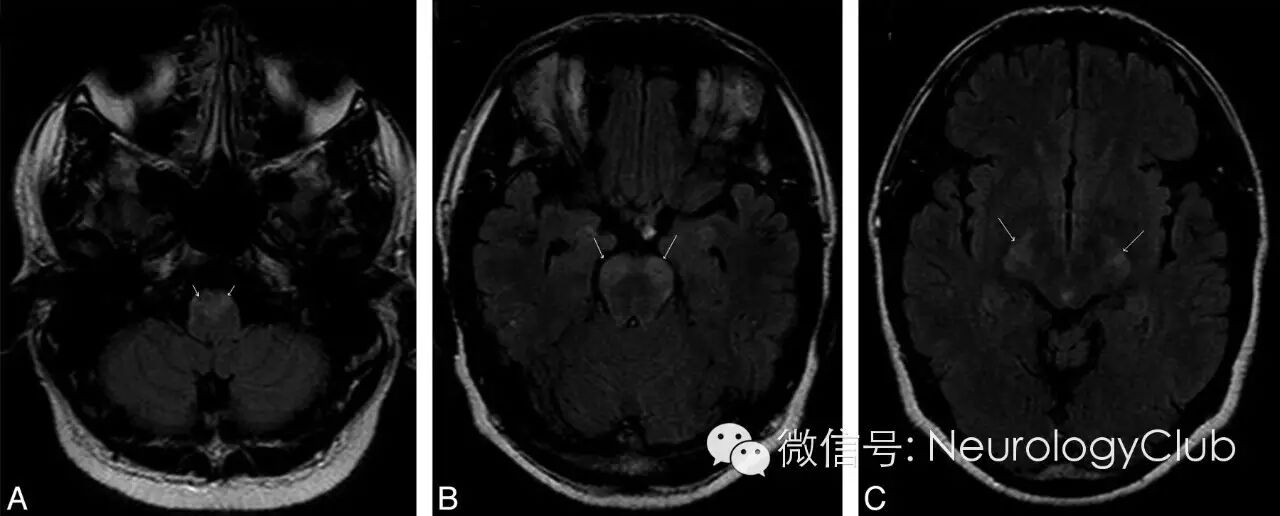

47岁男性,既往有义齿霜使用史,隐匿起病,4周时间逐渐出现双侧无痛性视力丧失,感觉异常和四肢轻瘫。神经系统查体提示左侧瞳孔传入障碍和视神经炎,左侧上运动神经元型面神经瘫痪,四肢轻瘫,反射亢进,下颌反射活跃,T6水平以下各种类型感觉缺失或减退。颈髓(图1)和头颅(图2)MRI如下。

(图2:头颅MRI黑水像可见累及延髓[A],脑桥[B]和中脑[C]锥体束的对称性高信号[箭])

铜是生命体必需微量元素,是关键金属酶(细胞色素C氧化酶,超氧化物歧化酶,多巴胺β羟化酶)的组成成分,在维持神经系统正常结构和功能中发挥重要作用。铜缺乏罕见,可由胃肠道手术,饮食中过量锌摄入,肠外营养以及吸收障碍综合征等引起。铜缺乏导致感觉共济失调性脊髓病,对称性的脊髓锥体束和后索受累,其临床与影像学特征与维生素B12缺乏相关的亚急性联合变性(SCD)非常相似,但周围神经病和视神经炎的报道少见。临床治疗效果并不一致。本例患者脊髓MRI上为铜缺乏性脊髓病的典型表现,同时存在明显的脑干锥体束受累。说明铜缺乏性脊髓病亦可合并脑干受累,尽管极其罕见。